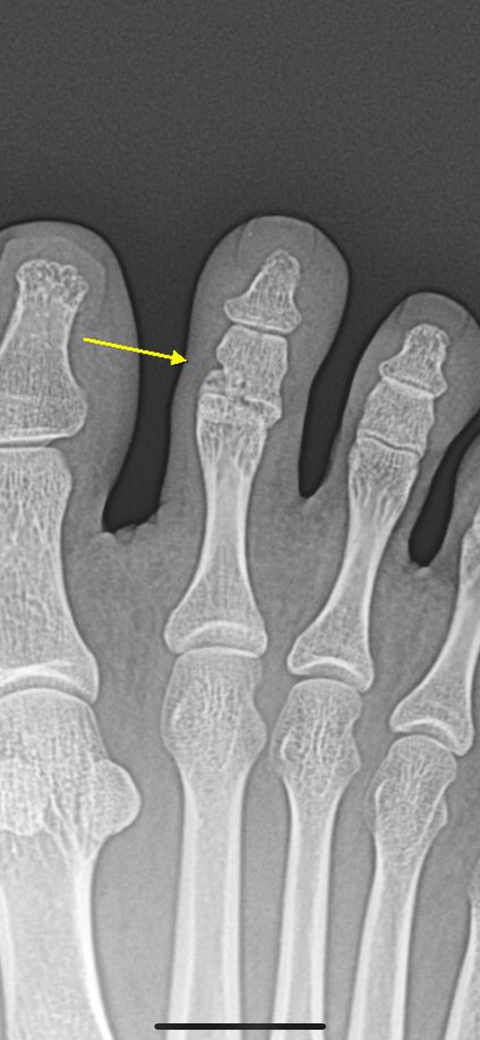

발가락 골절 많이 붙은 건가요? 엑스레이 봐주세요

발가락 핀수술하고 딱 31일 지났습니다

병원에서는 아직 반깁스 풀지 말라고 하시는데 사실 전 집에서 푸르고 다니긴 했어요 거의 외출이 없긴 했지만 집에서는 발날로 걸어다녔습니다.

지금 발 딛어도 아프지도 않고 발가락도 위아래로 통증없이 까딱일 수 있는데 운전하거나 걸어다니면 큰일날까요?

• 1번 째 사진

• 2번 째 사진